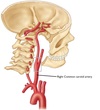

Name artery A

A - Right common carotid artery